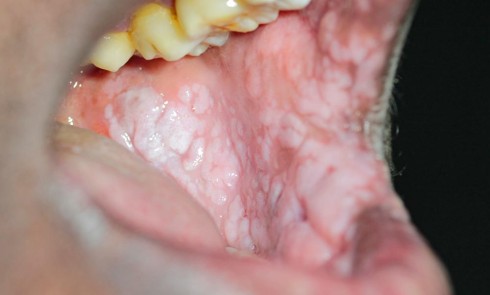

Motif de la consultation. Nourrisson de 45 jours, adressé en consultation pour une « tache blanche du palais ».

Histoire de la maladie. Les parents du nourrisson décrivaient une « tache blanche » palatine présente depuis la naissance, mais qui les inquiète du fait de sa persistance.

Interrogatoire. Le nourrisson était né à terme. Il ne présentait pas d’antécédent médical. Les parents ne décrivaient pas de changement de comportement ou de gêne lors de l’alimentation.

Examen clinique. On…